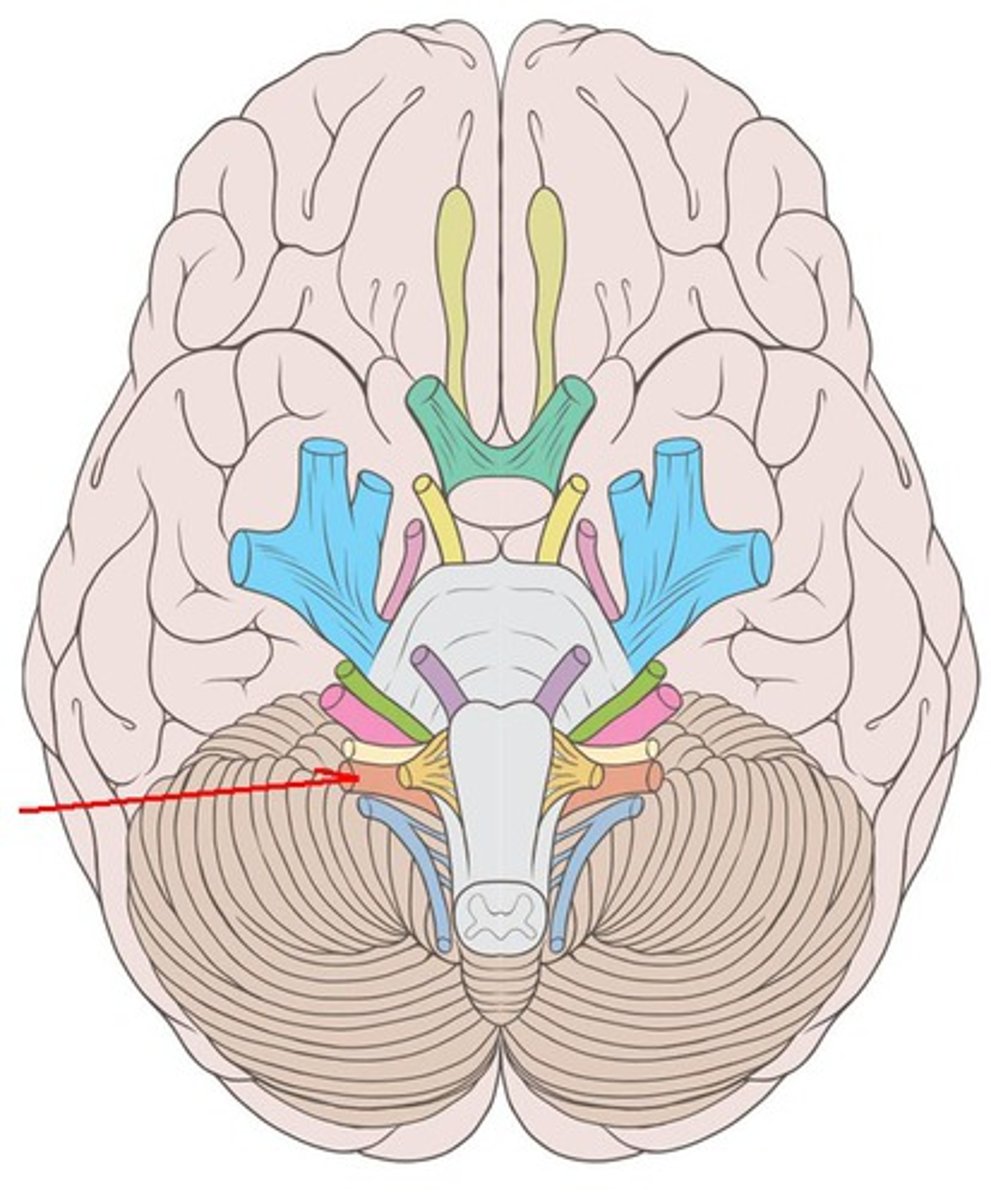

branches of olfactory nerve (cranial nerve I)

double check this

olfactory bulbs

olfactory tracts

double check this

optic nerves (cranial nerve II)

optic chiasma

optic tracts

CNIV (trochlear nerve)

CNVI (abducens nerve)

CNIII (oculomotor nerve)

CNVIII (vestibulocochlear) (acoustic nerve)

CNX (vagus nerve)